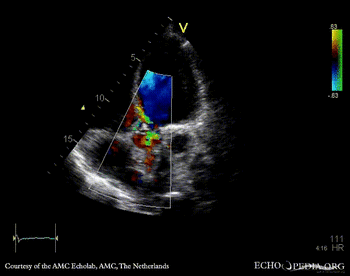

E00806.gif E00807.gif

A5CH: vegetation on aortic valve A5CH with Color Doppler: severe aortic regurgitation